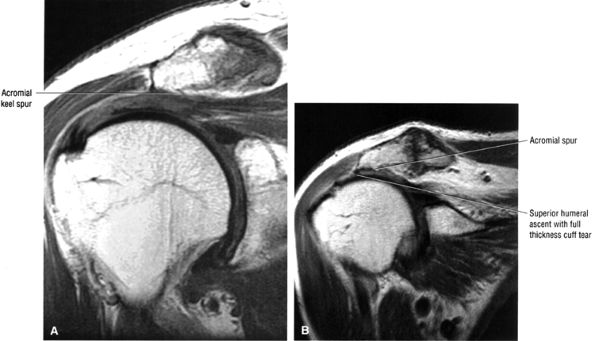

FIGURE 8.102 ● (A) The anterior undersurface of the acromion and the coracoacromial ligament form the coracoacromial arch. The subacromial subdeltoid bursa facilitates the passage of the rotator cuff and proximal humerus under the coracoacromial arch. (B) A superior axial image shows the anterior-to-posterior extent of the coracoacromial (CA) ligament perpendicular to the supraspinatus tendon. The fluid in the subacromial-subdeltoid bursa represents fluid between two serosal surfaces in contact with each other. One serosal surface is contributed by the undersurface of the coracoacromial arch and deltoid, and the other serosal surface is on the bursal side of the cuff.

|

![]() |